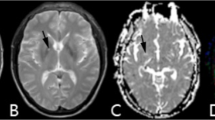

FA and MD

Compared with Test 1, in Test 2 the significant decreases of FA combined with increases of MD were detected in multiple sites of WM tracts (Fig. 6). In Test 2 vs. Test 1, the mean FA value was 0.436 (0.020) vs. 0.484 (0.026). p < 0.001; mean AD was 1.189 (0.030) vs. 1.145 (0.034), p < 0.001; mean RD was 0.575 (0.017) vs. 0.523 (0.048).

Statistical maps of comparison of fractional anisotropy (FA) and mean diffusivity (MD) values on a voxelwise basis.

Compared with baseline Test 1, subjects showed significant lower FA value and higher MD during high altitude exposure (Test 2), while showed significant higher FA value and lower MD after return to sea level two months (Test 3). p < 0.001 (corrected for multiple comparisons). Red indicates an increase; blue indicates a decrease.

Conversely, the increases of FA with the decreases of MD were detected in multiple sites of WM tracts in Test 3 (Fig. 6). In Test 3 vs. Test 1, the mean FA value was 0.451 (0.016) vs. 0.400 (0.022). p < 0.001; mean AD was 0.870 (0.019) vs. 1.164 (0.032), p < 0.001; mean RD was 0.423 (0.011) vs. 0.645 (0.037).